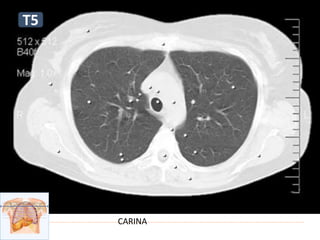

Niveles

 Carina (Tráquea): t5

CARINA

T5